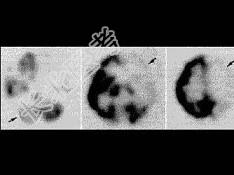

- 单项选择题男,74岁, 突发头疼、意识丧失7小时,行99Tcm-HMPAO脑血流断层显像如图, 最准确的诊断是 ( )

A、右侧小脑失联络

B、左侧TIA

C、左侧颞叶脑梗死

D、左侧顶叶癫痫灶

E、以上都不是